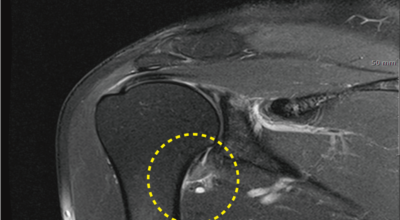

오십견이란 어깨의 통증과 어깨관절의 운동범위 제한을 특징으로 하는 질환으로 특히 50대 이후에 많이 발생함으로 오십견이라 이름이 지어졌으며 어깨관절이 얼어붙었다는 뜻으로 동결견(frozen shoulder)이라고도 합니다. 어깨관절의 운동성이 소실되기 때문에 옷 입기, 머리 감기, 물건 들기 등의 일상생활에 많은 어려움이 유발되며 통증으로 인해 잠을 못자는 경우도 대부분이 발생하게 되어요.

오십견 치료방법은 도수치료, 프롤로주사, 핌스(FIMS) 등 비수술적 방법을 적용합니다. 이 중 도수치료는 마취통증의학과 전문의의 정밀한 진단을 바탕으로 해부학적 지식이 많이 포함된 치료사가 진행하는 수기 치료입니다. 치료사가 손과 소도구를 활용하여 손상된 관절을 바로잡고, 경직되고 틀어진 주변 근육과 연부조직을 이완해 통증을 개선시켜 주어요.

수기로 진행하는 만큼 환자의 증상과 상태에 따라 강도를 유연하게 조절하는 맞춤 치료가 가능합니다. 프롤로주사는 근골격계 초음파 영상 유도하 주사치료 중 하나로 고농도 포도당 용액을 주입해 염증을 제거하고 손상된 조직을 재생하는 치료이며 근본적인 이유가 되는 것을 개선할 수 있어 근골격계 통증에 많이 적용되어요.